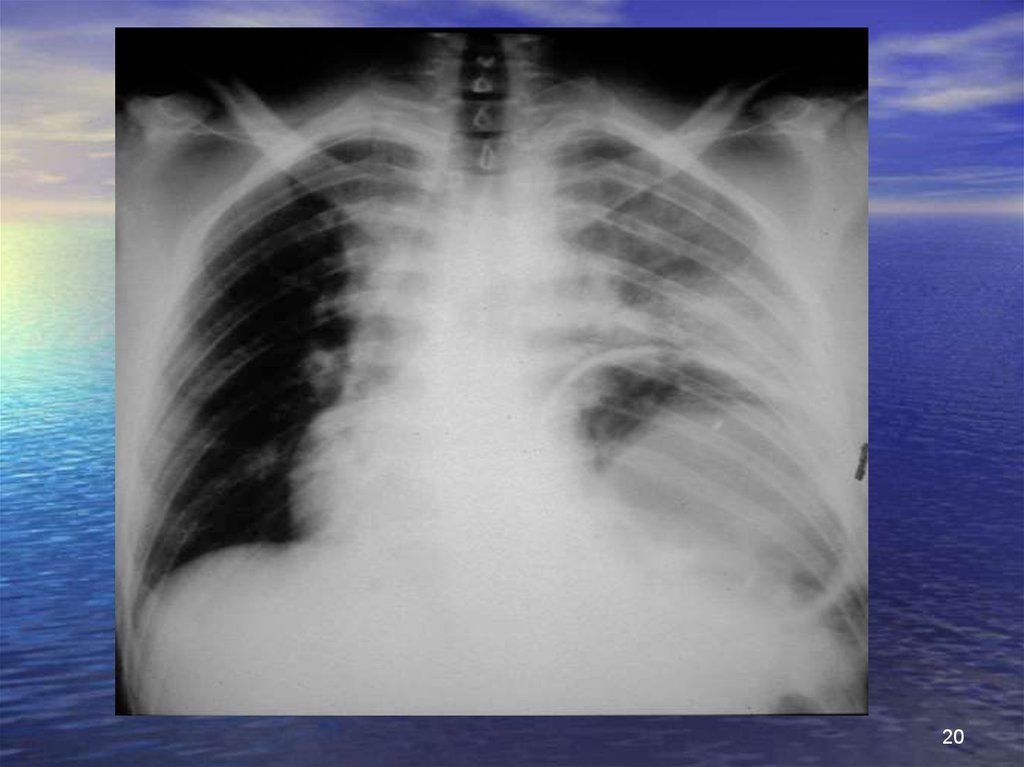

20.

20